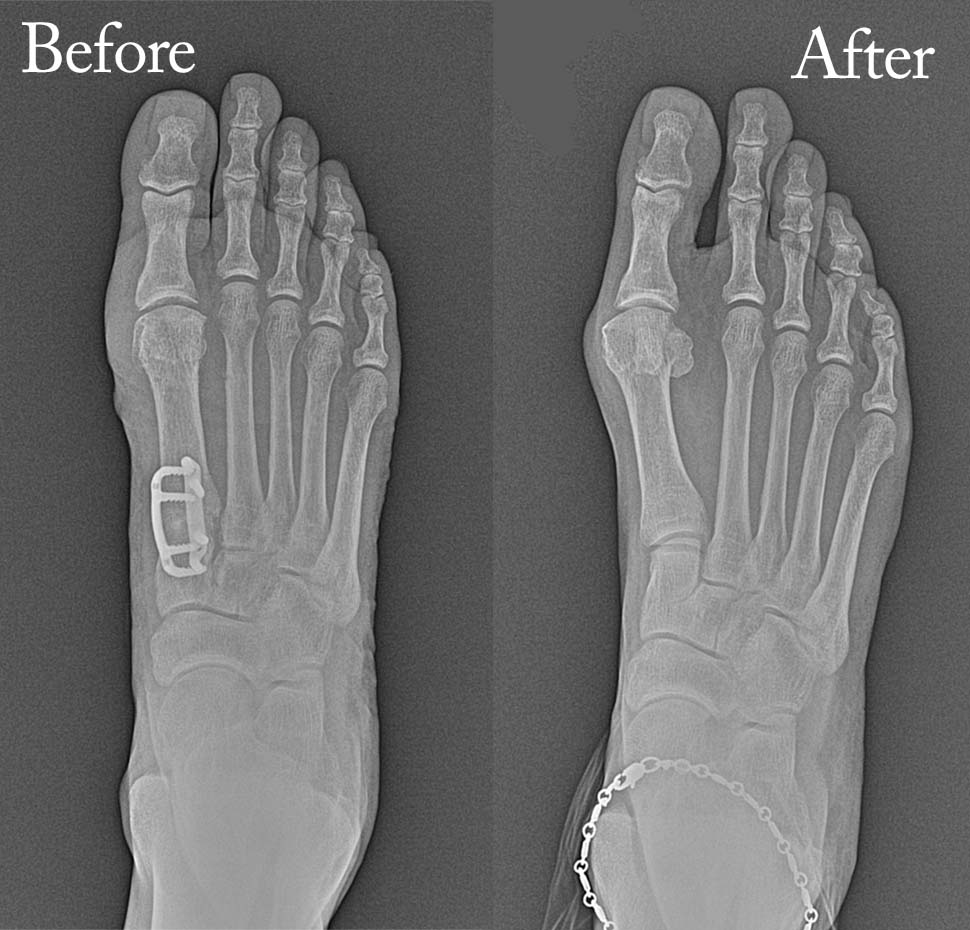

Foot pain might seem minor at first, but it often signals deeper issues that need medical attention. Two of the most common and painful conditions